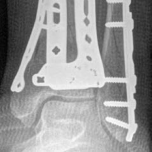

Removal of implants is not mandatory but recommended if implants are prominent under the subcutaneous envelope of the distal tibia. Implant removal should be undertaken only after healing is complete, ie, after 1 year at the earliest. This patient had achieved good radiographic and functional healing at the 1-year postoperative review (Fig 2.2-8 and Fig 2.2-9).

Fig 2.2-8a–b Postoperative x-rays at 1 year showing healed fractures, implants in situ, and limited tibiotalar arthrosis.

1. AP view.

2. Lateral view.